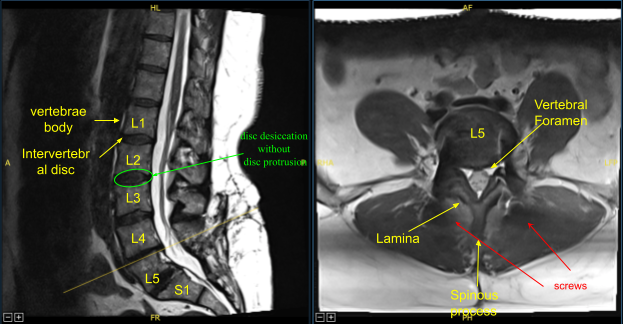

The patient presented to the office status post two previous lumbar surgeries performed by another provider including L5-S1 discectomy and L5-S1 TLIF. They developed recurrent back and lower extremity pain and symptoms and imaging showed adjacent segment disease with L4-L5 disc herniation, stenosis, as well as pseudarthrosis at L5-S1.

Next, we performed L4 laminectomy, bilateral facetectomy with Leksell rongeur, electric high-speed drill under continuous irrigation and Kerrison rongeurs resecting ligamentum flavum in piecemeal fashion and exposed thecal sac, decompressed it circumferentially and neurolyzed bilateral L4 nerve roots with Metzenbaum Penfield technique and confirmed with nerve hooks. Epidural bleeding was controlled with bipolar electrocautery and Surgiflo hemostatic matrix.

The thecal sac was retracted medially towards the right side with nerve root retractor. Annulotomy was performed with a 15-blade scalpel. Discectomy was performed with sequential pedal shavers and pituitary rongeurs. Endplates were prepped for arthrodesis with scrapers. We collected morselized autograft, bone shavings, and morselized resected spinous process and lamina.

Demineralized bone matrix allograft was placed into the interspace and then titanium expandable interbody device was placed under fluoroscopic guidance after sterilely draping the C-arm unit. AP and lateral imaging showed correct positioning and then the cage was expanded to the proper fit and the subsequent x-ray showed good positioning both in the midline and anteroposterior.